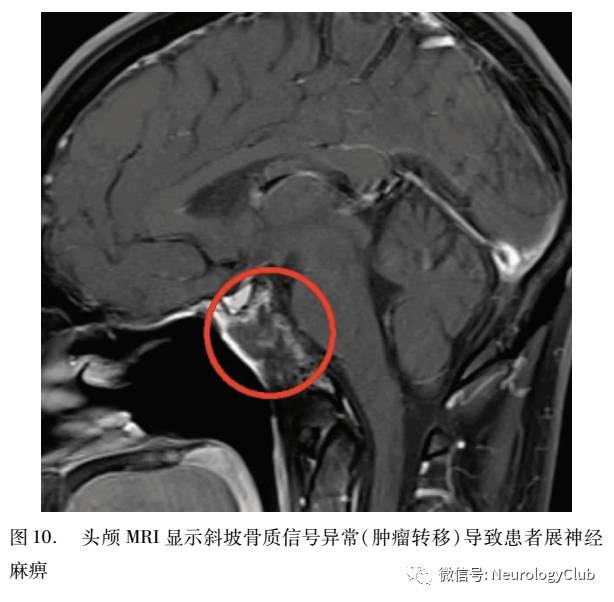

警惕:进行性展神经麻痹(压迫性);展神经麻痹伴有其他异常体征;拟诊微血管缺血展神经麻痹,但无恢复(图10、11),需进一步检查。